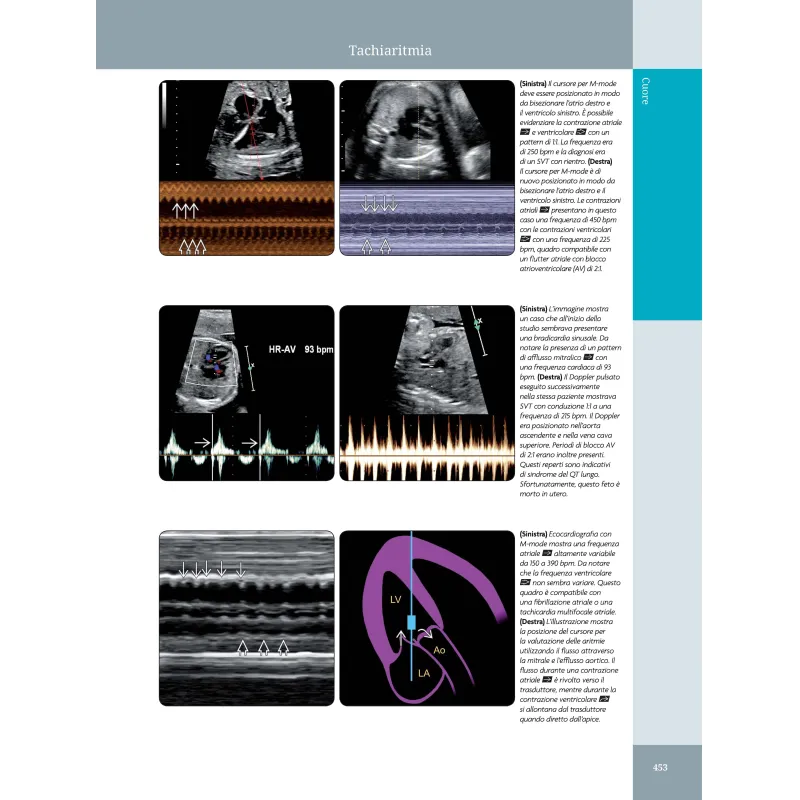

Ostetricia. Diagnostica per Immagini rappresenta una valida risorsa nel campo della diagnostica per immagini ostetrica. Grazie alla curatela di Gianluigi Pilu e alla traduzione di Elena Brunelli, Josefina Diglio e Anna Seidenari, questa edizione italiana basata sulla quarta edizione in lingua inglese, mantiene l'eccellenza accademica e professionale degli autori originali Paula J. Woodward, Anne Kennedy e Roya Sohaey. L’opera si distingue per la sua capacità di fondere la ricchezza visuale con contenuti scientifici di alto livello, offrendo una guida completa sulle più moderne tecniche di imaging in ostetricia. Il libro affronta ogni aspetto dell'ecografia ostetrica, dalle anomalie congenite maggiori e minori alle sindromi e ai disordini multisistemici, passando per la diagnostica delle gravidanze multiple e le condizioni materne che influenzano la gravidanza. La presentazione dell'edizione italiana sottolinea l'importanza di un testo stampato in un'epoca dominata dal digitale, valorizzando l'esperienza di lettura tradizionale senza rinunciare all'innovazione. Questa edizione, infatti, è arricchita da un'impeccabile qualità delle immagini e da una grafica di prestigio, rendendola uno strumento indispensabile non solo per gli specialisti del settore ma anche per la formazione di nuovi professionisti. La prefazione sottolinea gli sforzi collaborativi di un team di esperti, che hanno lavorato per portare ogni capitolo al massimo livello di eccellenza, con l'obiettivo di migliorare la diagnosi e la comprensione delle patologie fetali. Con oltre 5.000 immagini e video, questa risorsa si impone come una delle più complete disponibili sul mercato per chi si occupa di imaging ostetrico.